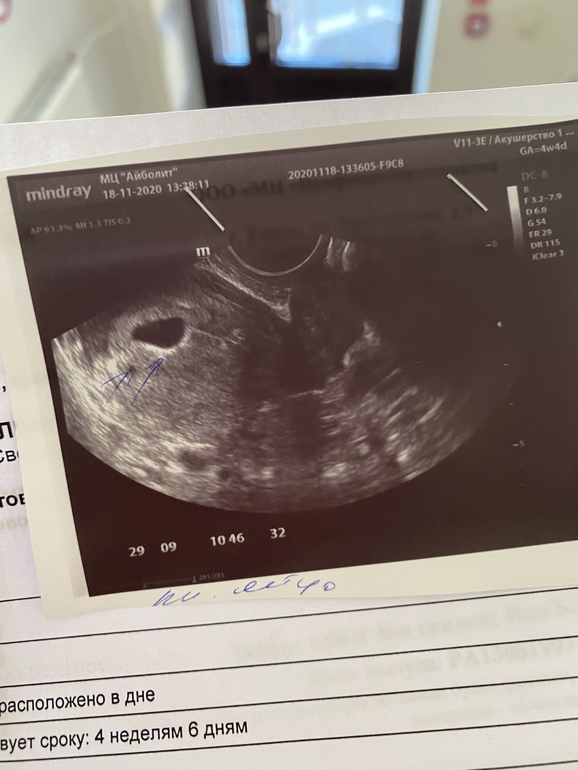

Доброе утро, девочки. Вчера сходила на узи

Акушерские у меня 4 недели и 4 дня

Плодное яйцо сказали 10 мм

По овуляции мне кажется, что у меня 5н и 2 дня

Это нормальный размер? Переживаю немножко, хотя там вроде даже эмбриончика видно, узистка сказала 0,9 мм

Вопрос вот в чем, это нормальный размер ПЯ?